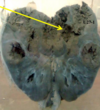

26

Section in? Describe Arrows Diagnosis?

Liver Rt lobe showing round non capsulated malignant greyish weight mass. Cut section is nodular and regeneration nodules are small and yellow Pink: HCC Black: Cirrhosis Hepatoma of cirrhosis